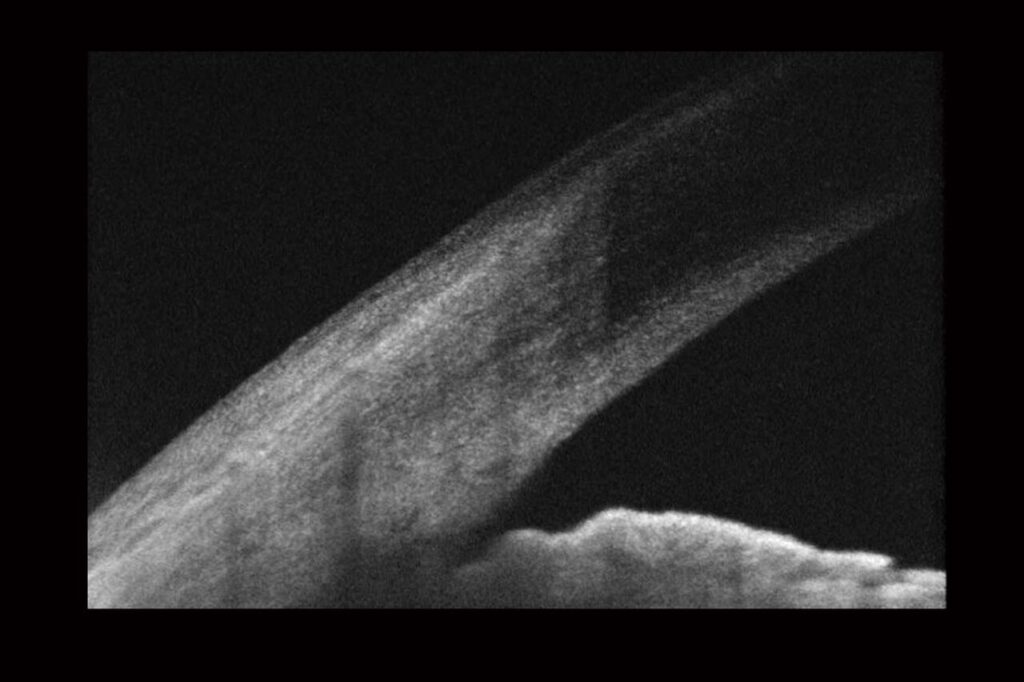

The three main tests for glaucoma are; An assessment of the optic disc at the back of the eye, a pressure check & a fields assessment to map your peripheral vision.